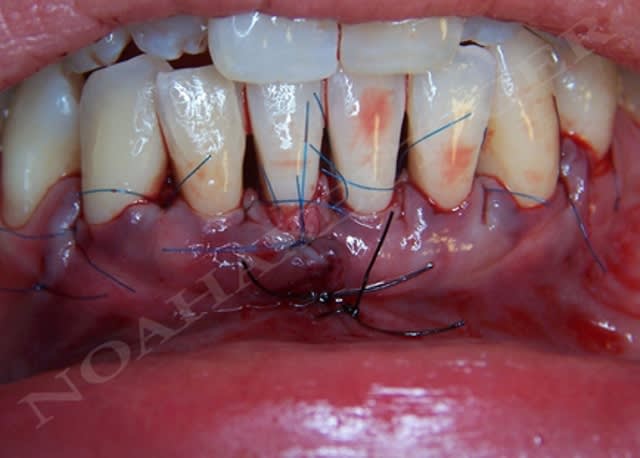

noahaxeltiger-olivier

13/02/2009 à 20h30

lors de la cicatrisation on remarque une amélioration gingivale au niveau de 32 et 42 mais malheureusement une récession persistante au niveau de 31 et surtout 41.

Lors de l'analyse des différents facteurs de cicatrisation, je note alors que 31 et surtout 41 sont mobiles grade 1 !!

Du coup, controle occlusal, contention et opération numero 2 (date de la semaine dernière) :

Oui mais de façon non- contradictoire mais plutot comme co-facteur d'échec sur 41, il n'y a que sur celle ci que le greffon n'était pas recouvert par le lambeau, d'où des conditions moins favorables, d'où une nécrose de la partie non recouverte, et de là une nécrose de la partie recouverte voisine par diffusion de toxines (qu'en penses tu?).